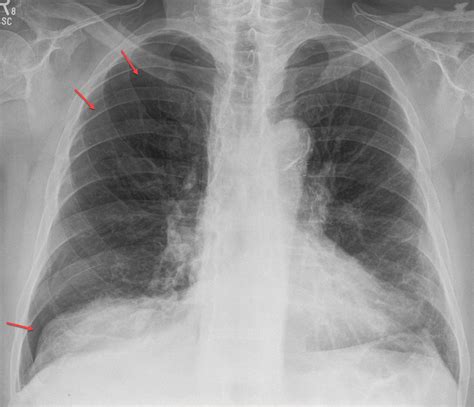

Chest X-rays are the primary imaging modality used to diagnose pneumothorax. They provide a clear view of the lungs and pleural space, allowing radiologists to identify the presence of air. The key features to look for in a pneumothorax in X-ray include:

• The absence of lung markings beyond the visible edge of the collapsed lung

• A visible line representing the edge of the collapsed lung

• Hyperlucency (increased brightness) in the affected area

• Deviation of the mediastinum (the central compartment of the thorax) towards the unaffected side

Simple Pneumothorax

A simple pneumothorax is the most common type and occurs when air enters the pleural space without any underlying lung disease. On an X-ray, it appears as a thin line separating the lung from the chest wall, with no visible lung markings beyond this line.